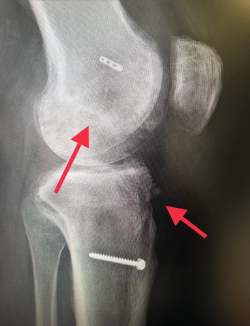

Figura 1. Laxitud en el cajón anterior. Radiología forzada.

Desde el punto de vista clínico, se consideran motivo de revisión quirúrgica aquellos casos en los que exista un desplazamiento anterior comparado con el contralateral mayor de 5 mm, pivot shift de alto grado, dolor, inflamación, sensación subjetiva de inestabilidad y limitación funcional para las actividades de la vida diaria o deportiva(9,10). Algunos autores han rebajado esta cifra a 3 mm con respecto a la rodilla contralateral o 10 mm de desplazamiento absoluto en el plano sagital(11)(Figura 1).